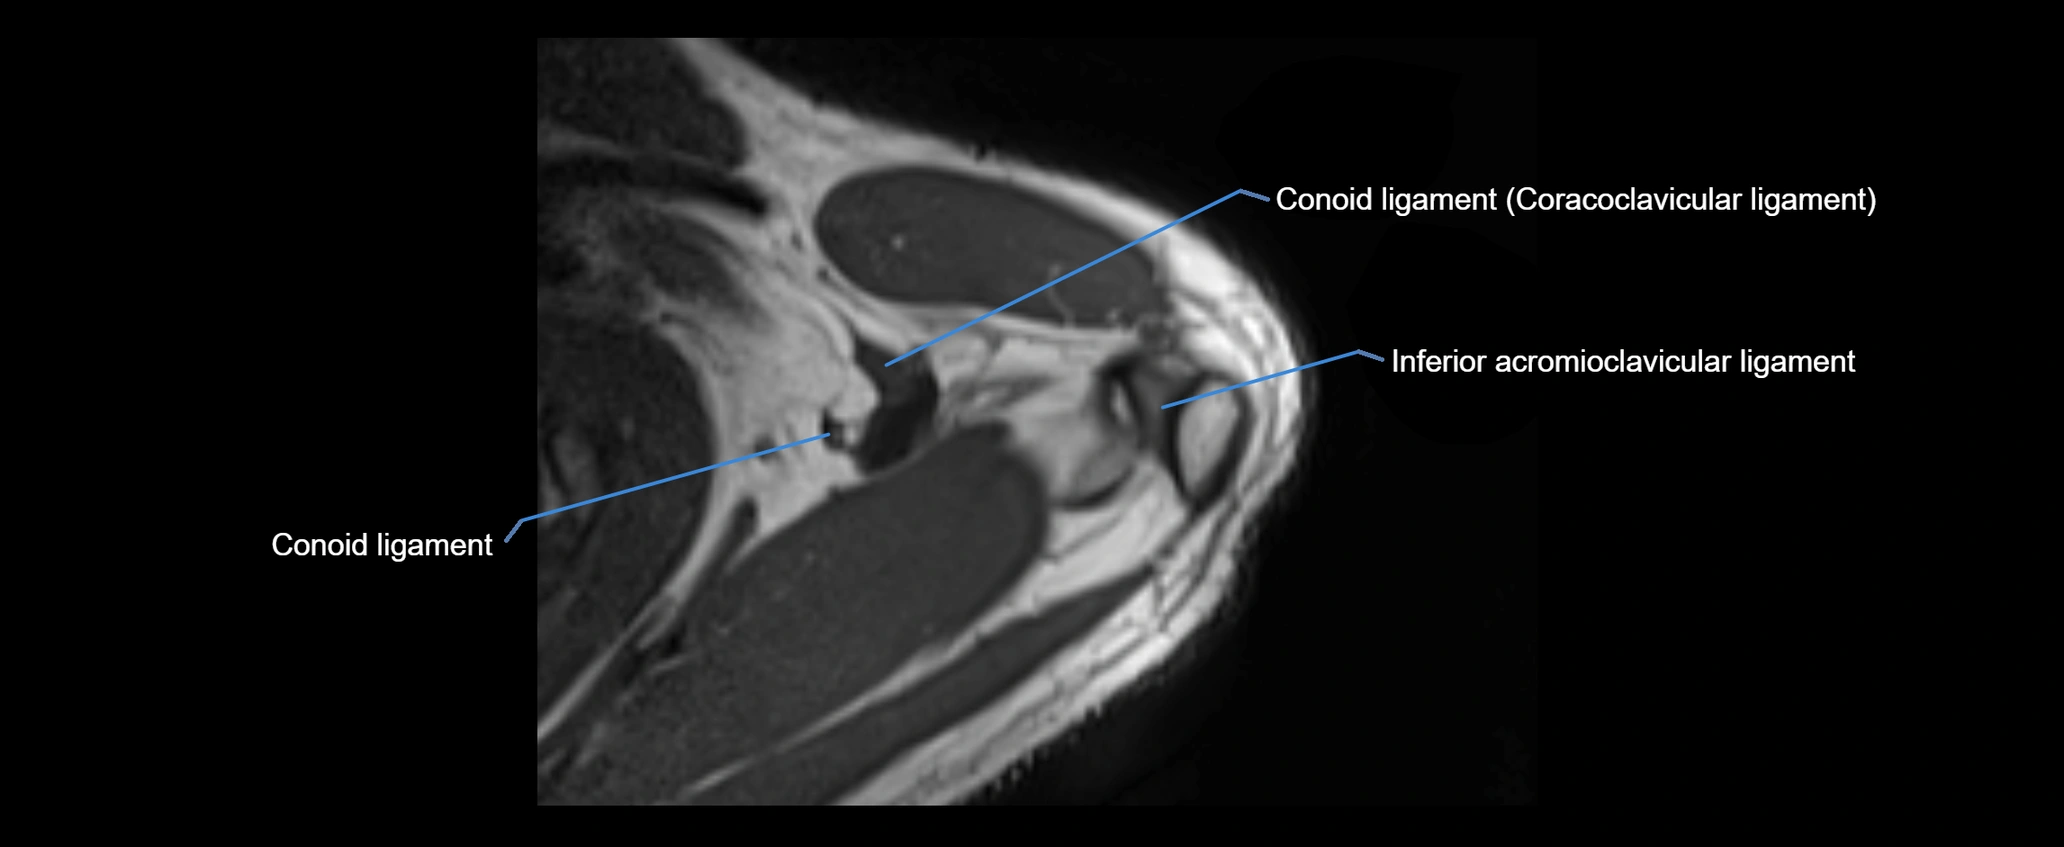

CT image

image